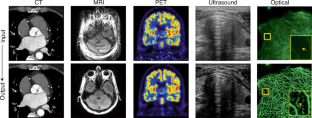

Molly Freimuth (CT image); Christopher Hardy (MR image); Dawn Fessett (ultrasound image).

Molly Freimuth (CT image); Christopher Hardy (MR images).

Froedtert & Medical College of Wisconsin (CT images); Christopher Hardy (MR images); Quanzheng Li (PET images).